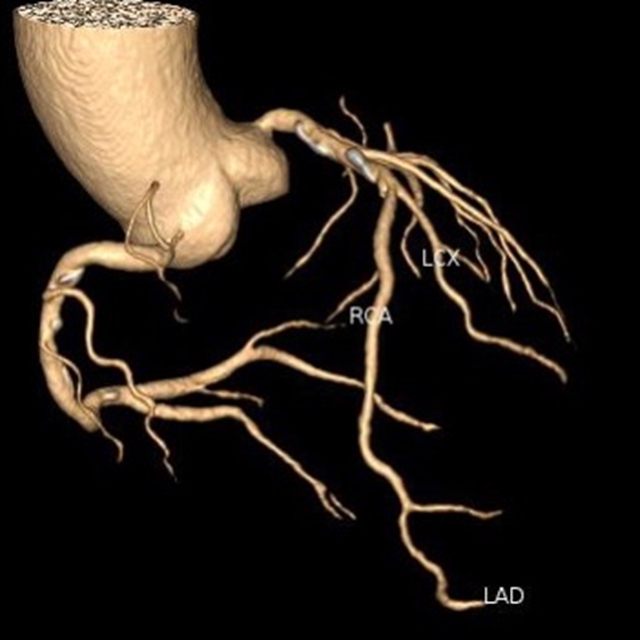

“一站式”CT检查

胸痛三联征“一站式”CT检查是指通过一次扫描、一次注射造影剂可同时显示冠状动脉、肺动脉及主动脉三种血管的图像,有助于早期、快速诊断,同时可以最大程度降低辐射剂量。因此已成为目前评估急性胸痛患者的首选检查方法。

1.急性心肌梗死的诊断:“一站式”CT检查可以快速识别冠状动脉的狭窄或堵塞程度,及时帮助医生确认诊断,制定进一步的治疗方案。